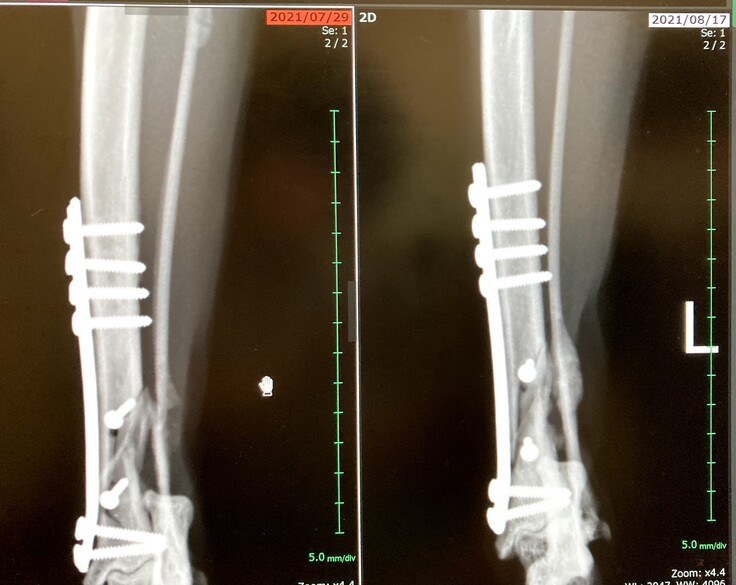

今回このくーちゃんが左後ろ足を開放性剝離骨折してしまいました。骨が3分割と小さな骨に分かれてしまっていてプレートを入れ小さい骨はピンで止めていただき手術は大成功しました。しかし創部に感染があった為術後も入院が長引きました。退院して2日後又発熱しぐったりし受診、感染からの熱か再入院。その退院の2日後にまた患部が凄く熱くぐったりし受診。今回は手術の部位が再度骨折してしまっていました。毎日ケージの中でほぼほぼ寝たきりであったのですが何故か再度骨折。かなり痛みもある様で可哀想に熱もでていました。私は死んでしまうのではと夜中に何度も見に行く日々が続きました。

悲しいことに手術してもらった所が再度骨折。

上が7月10日、下が15日 真ん中の小さい骨がずれてピンが横を向いてしまっています。

9月17日現在、骨折の方は新しい骨が少しづつ出来てきていました。心配していましたが、良かったです。少しほっとしました。しかし骨形成は遅くまだこれから1か月半位安静必要だそうです。今まで寝てばかりでしたが、最近はお座りも出来るようになってきました。

9月17日上の写真です。空いていた穴が少しずつ塞がって来ているとの事です。